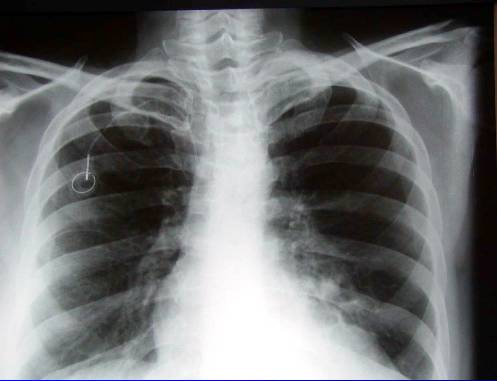

Diferenciální diagnostika

Recidiva Ca mammae

(generalizace do plic)

nebo

Duplicita Ca plic

2.Duplicita (pac.H.M.– RTG,CT, CT-PET,UZ,bronchoskopie,cytologie, chirurgická intervence -biopsie -karcinoid)

Duplicita (pac.H.M. . ––RTG,CT,UZ, CT-PET,bronchoskopie,cytologie, chirurgická intervence-biopsie -karcinoid)